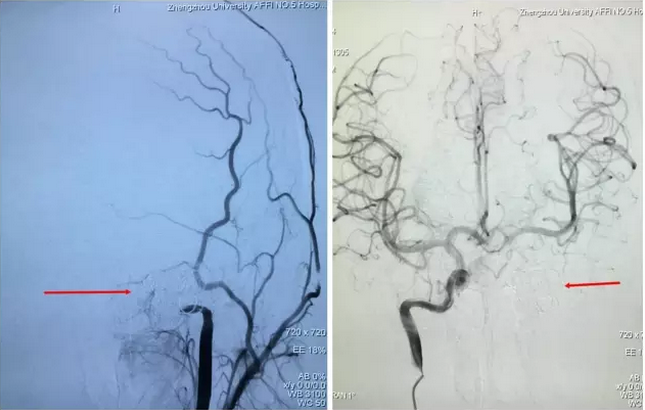

寿记新教授认为,该患儿动脉瘤多发不适宜行传统开刀手术,更适合于血管内介入治疗。于是在认真分析脑血管造影结果后制定了详细而缜密的治疗计划:右侧椎动脉动脉瘤行支架辅助动脉瘤栓塞,左侧颈内动脉海绵窦段巨大动脉瘤行动脉瘤栓塞+颈内动脉闭塞。手术过程非常顺利,术后造影:左侧颈内动脉未见瘤样扩张及远端显影,颈外动脉反流;右侧颈内动脉造影,左侧大脑前、中动脉显影良好,左侧颈内动脉无反流(图2)。术后李同学仅仅住院1周便顺利出院了,头痛症状完全消失并且没有留下任何后遗症。

图2术后脑血管造影:左侧颈内动脉巨大动脉瘤完全消失。